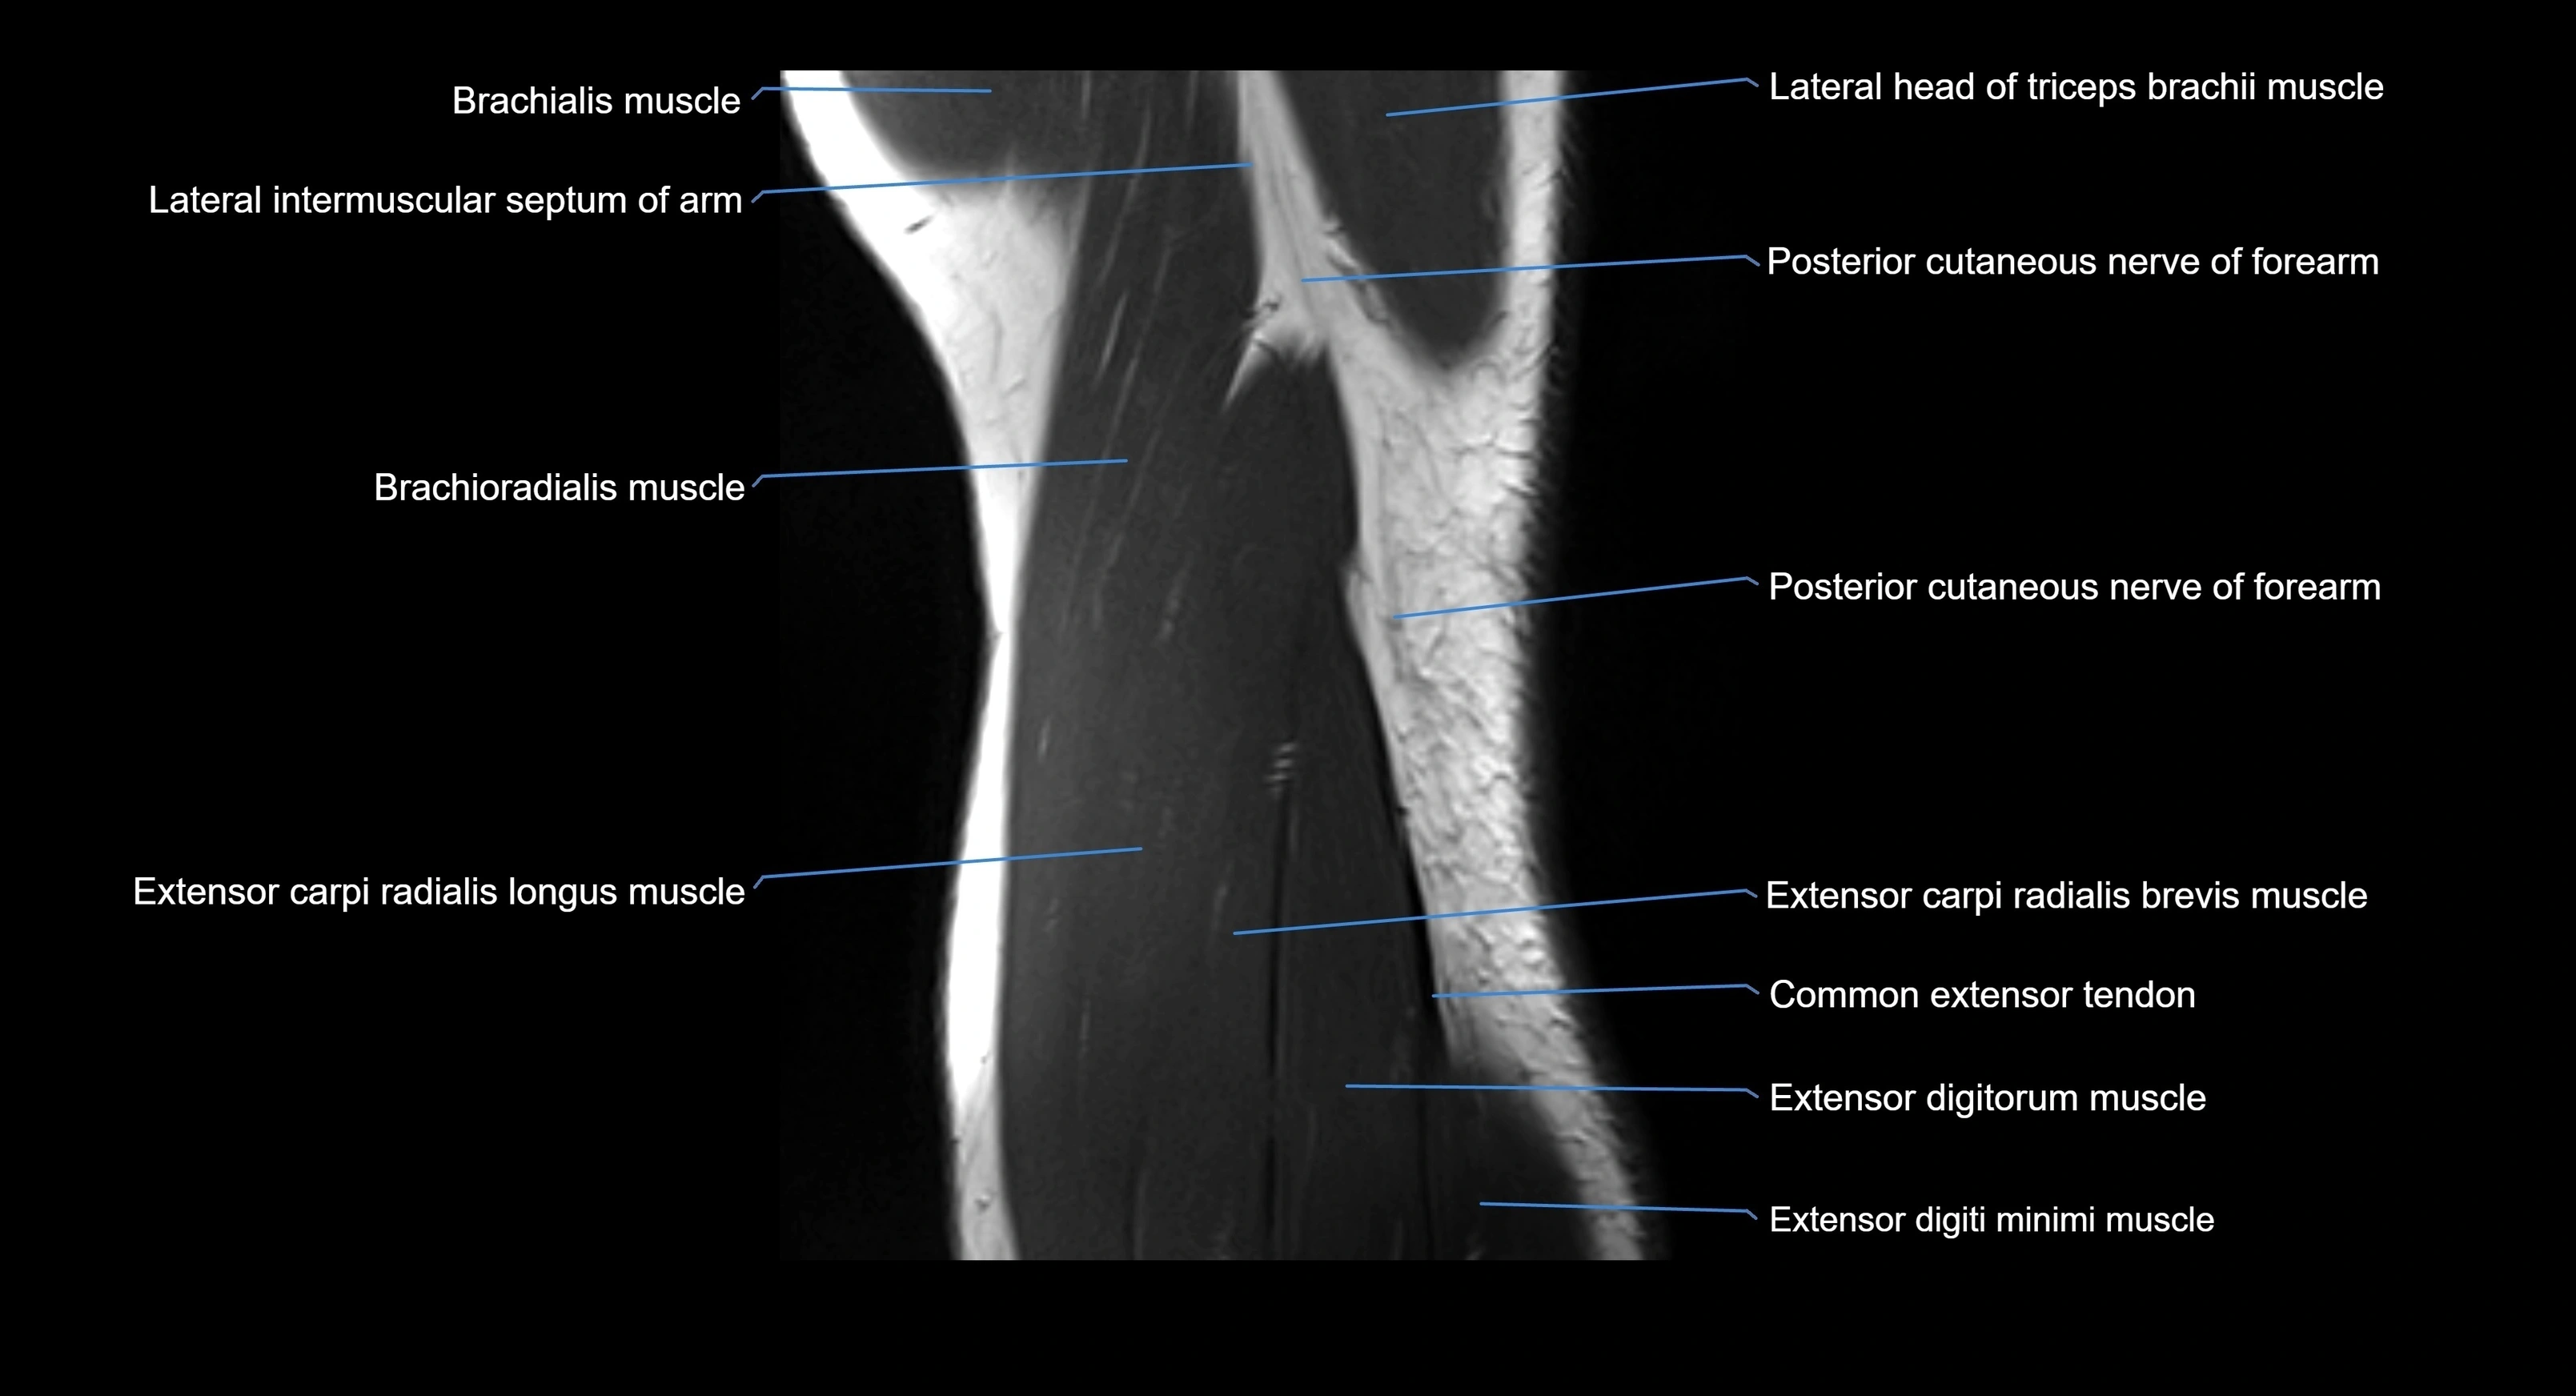

MRI image

image